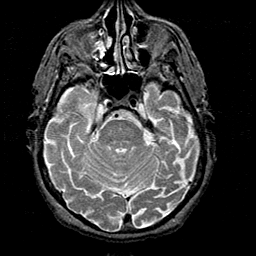

Alzheimer's disease MR T2-weighted -- Slice #14

[Home][Help][Clinical][Tour 1][Tour 2] Slice 14